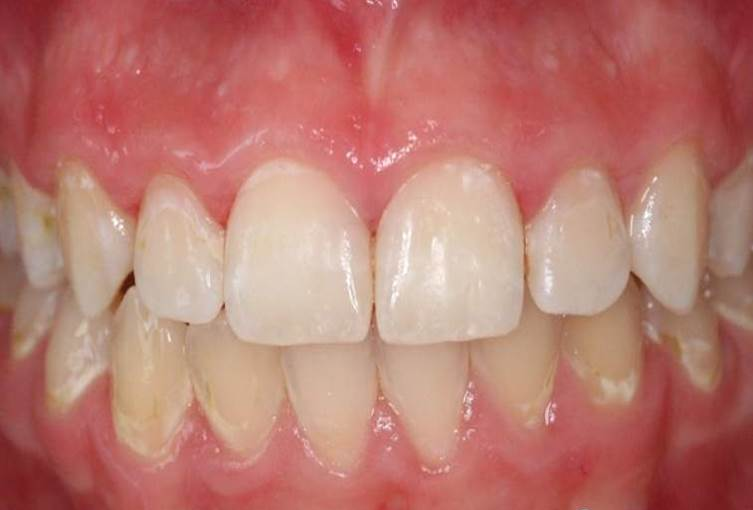

9、治疗后

dmg口腔材料怎么使用DMG-Icon专利之渗透树脂(内含操作视频)_https://www.jmylbn.com_新闻资讯_第14张